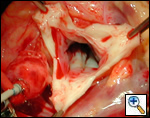

The operative approach is through a median sternotomy with the use of cardiopulmonary bypass and bicaval venous cannulation. The first dose of cold blood cardioplegia is antegrade; the remaining doses are retrograde.

High ascending aortic cannulation adjacent to the innominate artery for maximum exposure of the ascending aorta and to allow length for positioning of the patch in the ascending aorta.

One dose of antegrade cardioplegia followed by retrograde cardioplegia.

Pulmonary homograft or pericardial patches (tanned in glutaraldehyde) for the “shields”. These patches should not be too large – this will lead to aortic insufficiency.

First coronary sinus incision in noncoronary sinus to facilitate exposure of the incisions into the coronary orifice sinuses.

In most cases, the right coronary artery sinus should be opened to the left of the coronary orifice and the left coronary artery sinus to the right of the coronary orifice. Occasionally one may not have enough room between a coronary orifice and the aortic valve; in this case the incision site should be tailored to the situation.

Ensure similar orifice sizes between the proximal and distal ascending aorta after patch augmentation by the use of a sizing dilator.

Transesophageal echocardiography to assess completeness of repair, coronary blood flow postoperatively, wall motion abnormalities, and adequacy of aortic valve.